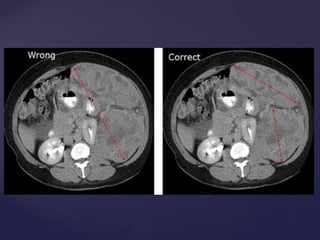

 En primer lugar, identificar el

diámetro más largo de un

ganglio linfático o la masa

ganglionar (17.6mm en este

ejemplo) y luego medir el

diámetro más largo

perpendicular a que a medida

que el eje corto (10.6mm en

este ejemplo).

 10.6mm en el eje corto define

este ganglio linfático como

patológica, pero no mensurable.

Como tal, se registrará como

una lesión no objetivo.